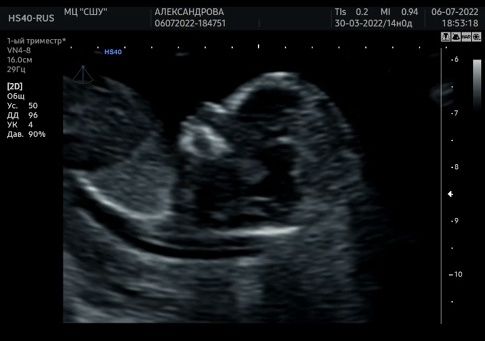

В первый скрининг не стала себя нагнетать, т.к. там по размерам нос в нижней границе нормы, ТВП наоборот был в верхней, врач хотела кровь cito чтобы сделали, но не успели, кровь уже отправили. (как я сейчас понимаю, она не хотела меня пугать).

Мы с мужем никуда не торопясь, через несколько дней сходили в Самарскую школу ультразвука. Там узи длилось не 5 минут, спросили говорить ли пол, три раза посмотрели со всех возможных сторон-девочка. Размеры носа и ТВП в норме, никаких пороговых значений, ребенок здоров. + дали флешку с видео и переходником для телефона.